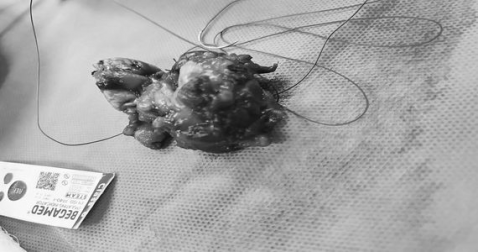

نجاح عملية رفع ورم الغدة اللعابية لمريضة خمسينية في مستشفى القرنة العام بالبصرة

نجح فريق طبي جراحي في مستشفى القرنة العام بالبصرة بإجراء عملية فوق الكبرى لرفع ورم كبير في الغدة اللعابية تحت الفك الأيسر لمريضة تبلغ من العمر ٥٣ عاماً وتعاني من مرض السكري وألم مستمر وتورم في الوجه.

وذكر اعلام دائرة صحة البصرة :" تم رفع الورم بالكامل تحت التخدير العام، وأُرسل للفحص النسيجي. بإشراف الدكتور سيف منعم دهيس أخصائي الأذن والأنف والحنجرة، وبمشاركة الدكتور محمود مؤيد ضمد أخصائي التخدير،.

واضاف:" نُقلت المريضة إلى ردهة الجراحة العامة للمتابعة، وهي الآن بحالة صحية جيدة، ./انتهى